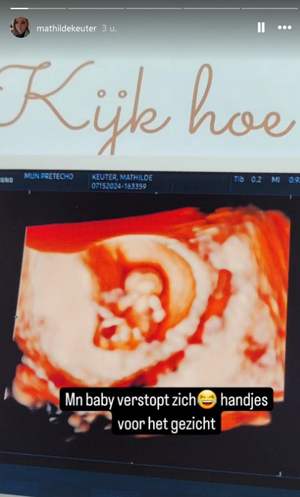

In haar Instagram Stories deelt ze zowel foto’s als filmpjes van de echo. “Mijn baby verstopt zich”, lacht ze erbij. “Handjes voor het gezicht.” Wil de baby nog niet in beeld? We gaan het snel genoeg merken in het nieuwe seizoen van Urk!, want Mathilde heeft al laten weten dat we haar tweede kindje wel in de serie te zien krijgen. Dat is niet het geval voor haar eerste spruit.

Mathilde is opnieuw tegelijkertijd zwanger als haar zus Gerda. Die is wel ruim tien weken verder in haar zwangerschap en staat al op het punt dat ze rustiger aan gaat doen. Zo was het concert van Taylor Swift het laatste waar ze tot de bevalling heen ging. Mathilde is nu tien weken en drie dagen onderweg.